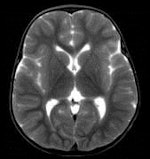

CT and MRI exams were performed during evening and night shifts at times when scanners were not in use for the hospitals' patients. The bodies, contained in sealed body bags, were imaged in the supine position. Two radiologists first independently interpreted the exams, preparing individual reports. They subsequently prepared a consensus report. Additionally, brain scans were reported by a specialist neuroradiologist, and a specialist cardiac radiologist also interpreted findings and prepared a report. All radiologists limited their reports to noting only findings that could pertain to cause of death.

Based on their findings, the radiologists determined that an autopsy could have been avoided for 34% of the cases based on CT exam reports, 42% based on MRI reports, and 48% based on consensus reports. In many cases, imaging proved to be better than autopsy in detecting pneumothorax, intracranial pathologies, and some fractures, the authors wrote.